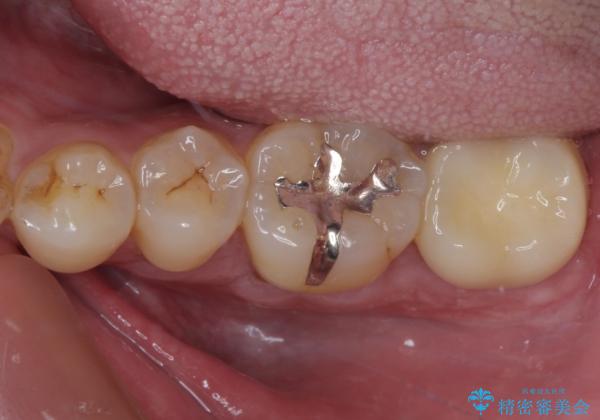

- 職場近くで通っていた医院の先生が体調不良で診療できなくなったとのことで、転院されてきた患者様です。

既に根管治療を終えている状態での来院で、クラウンを装着を希望されていらっしゃいました。

レントゲン写真より根管治療のやり直しをお勧めしたところ、ラバーダム使用下で処置を行うことを希望されたため、根管治療を行った後にオールセラミッククラウンにて補綴治療を行うこととしました。